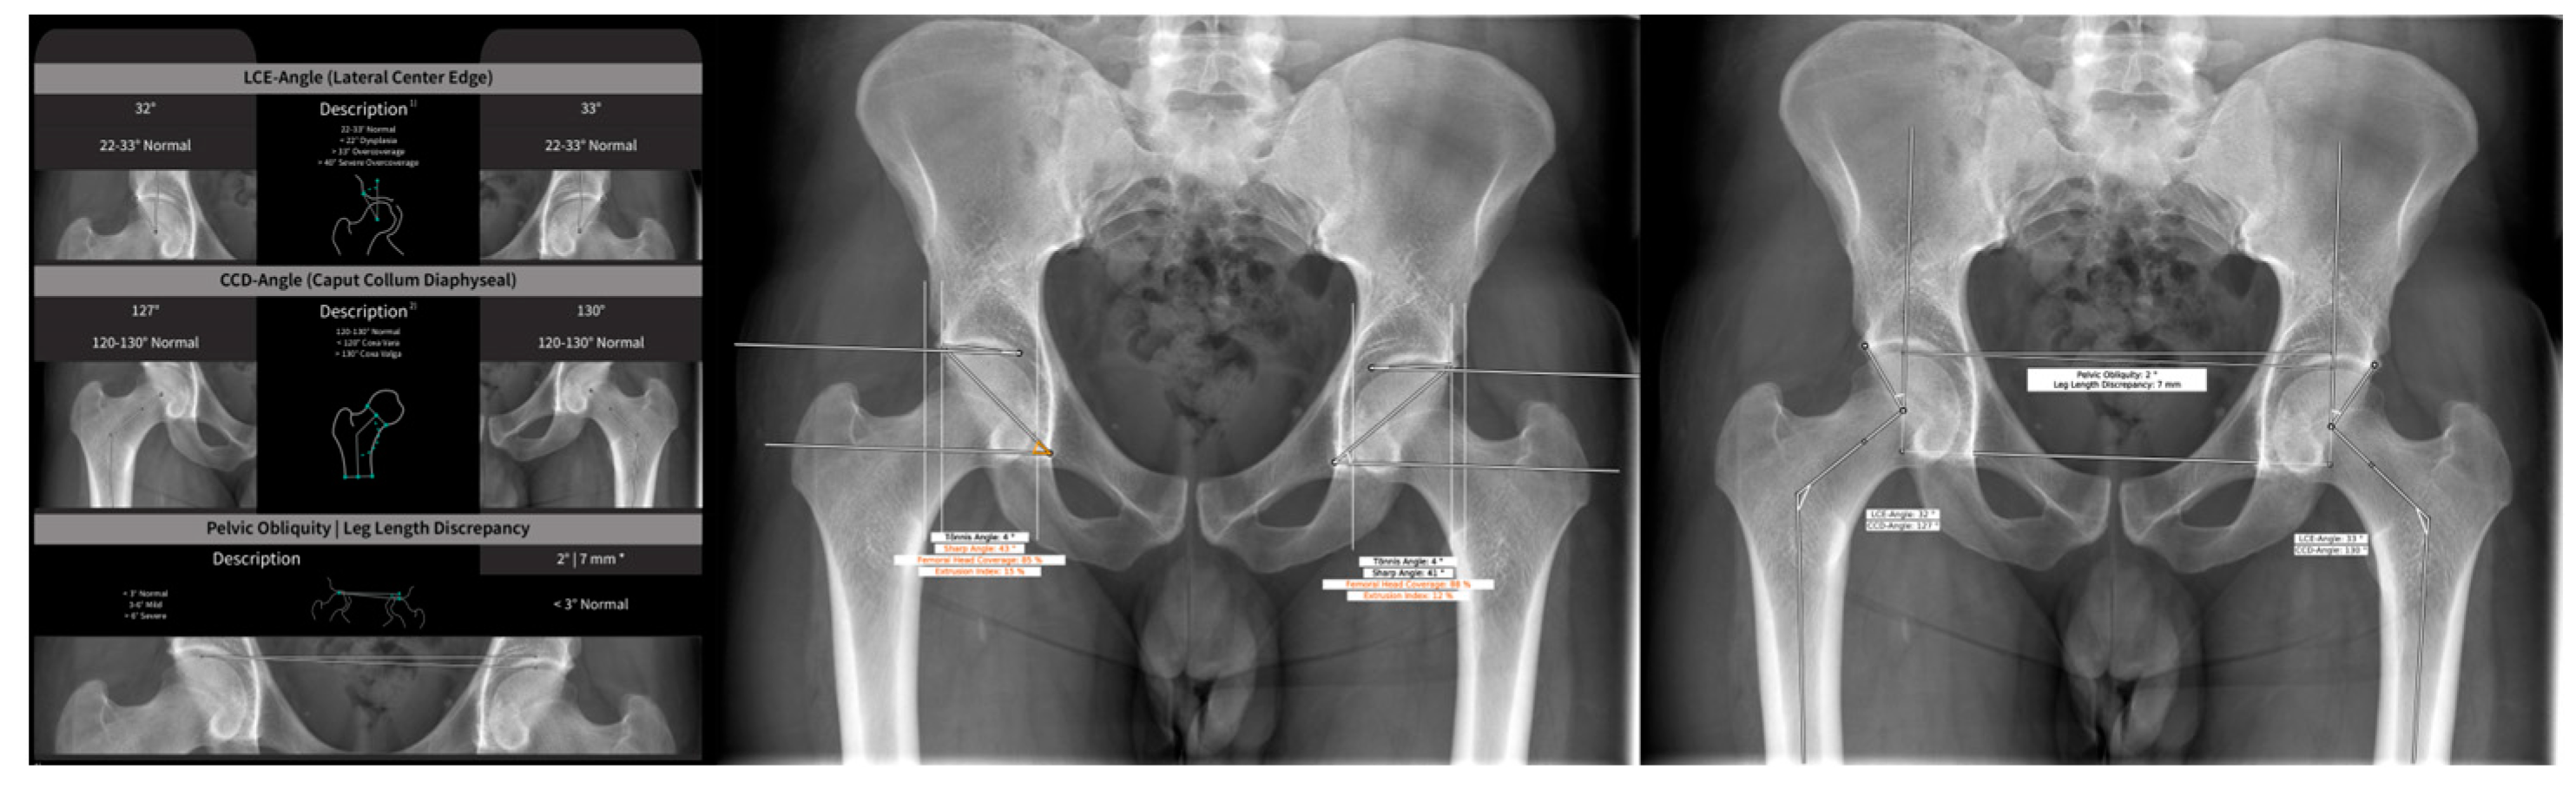

| Archer et al., 2022 [14] | Detection of Hip dysplasia through lateral CE, CCD, pelvic obliquity, Tönnis angle, Sharp angle, femoral head coverage using HIPPO™ | HIPPO™ used for Identification of bony landmarks. 256 ap hip radiographs for testing. Compared to three medical students who underwent instructions form one senior radiologist. | ICC for lateral CE: 0.71–0.86, for CCD: 0.62–0.79, for pelvic obliquity: 0.83–0.98, for Tönnis angle: 0.82–0.90, for Sharp angle: 0.74–0.86, for femoral head coverage: 0.5–0.73. |